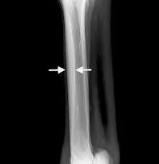

Cannon Bone Sequestrum + Osteomyelitis

Et: Focal impact injury → cortical fragment death → sequestrum formation

Cs: Draining non-healing wound

Dt: Rads

Tx: surgical debridement and drainage

Splints

Et: Exostosis of MC/MT II & IV

Tearing of IO lig → periosteal reaction → new bone formation

Cs:

Acute: variable lameness

Chronic: painless bony enlargement

suspensory desmitis = blind splint

Tx:

Acute: cold therapy, topicals, steroid injection, bandaging, rest

Blind splint: surgical removal of periosteal/bony growth